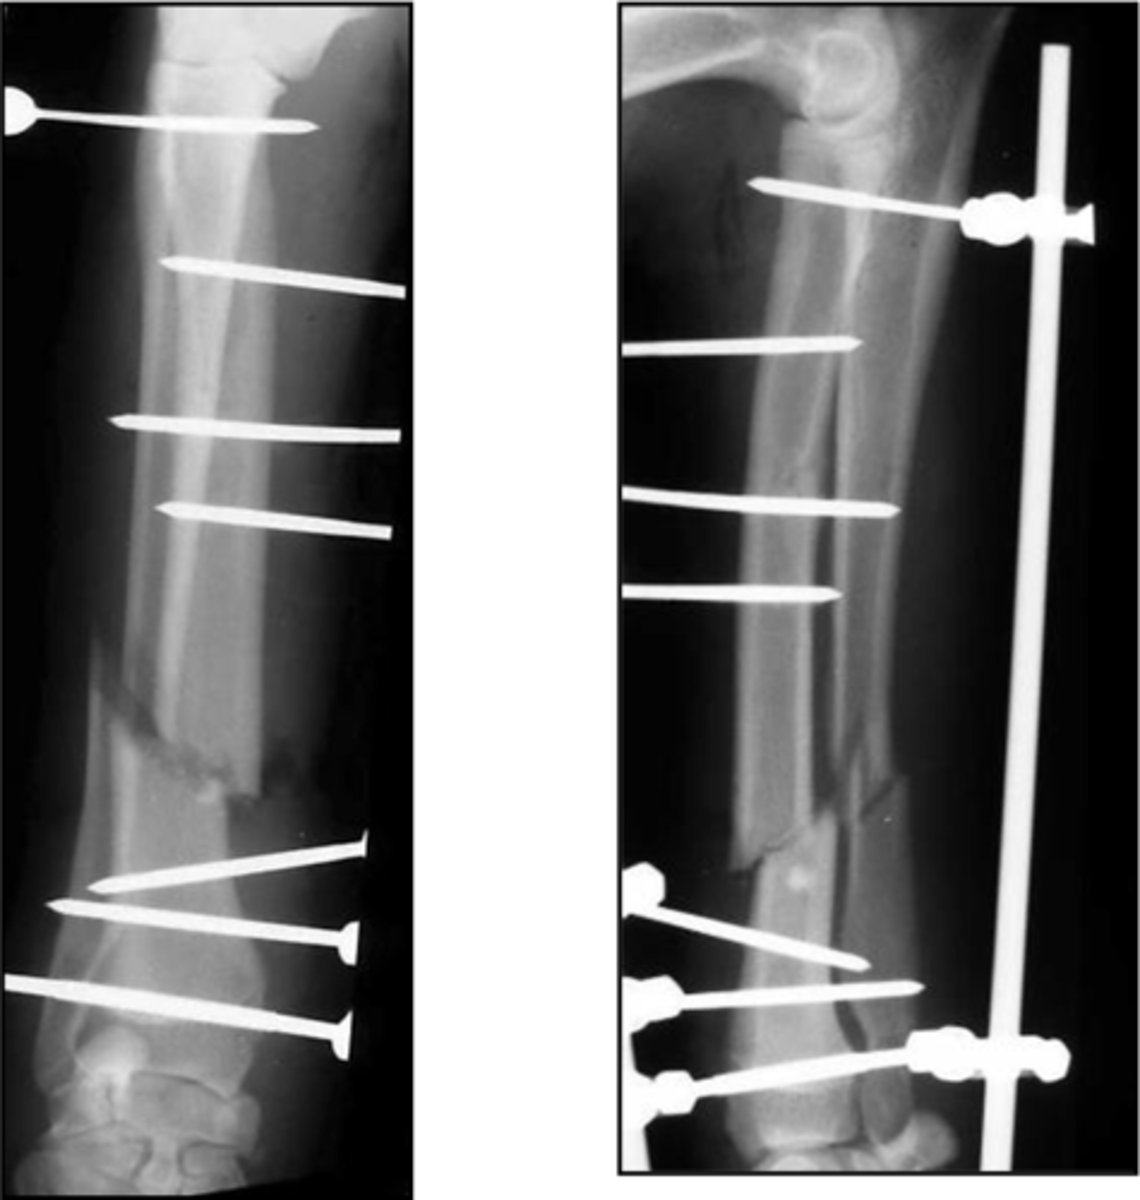

application of external fixator to radio-ulnar fracture

-uniplanar or biplanar

-unilateral or bilateral